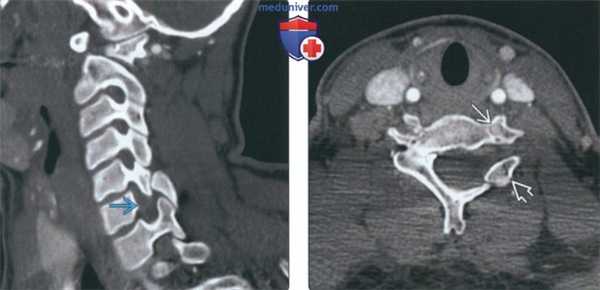

(Слева) На косой корональной КТ в костном окне определяется врожденное нарушение формирования левой ножки С6, патологические изменения дуги и гипоплазия суставного отростка. Такое сочетание патологических изменений приводит к формированию широкого межпозвонкового отверстия.

(Справа) На аксиальной КТ в костном окне определяется врожденное нарушение формирования левой ножки С6, дуги слева и гипоплазия суставною отростка. Обратите внимание, что левая позвоночная артерия имеет нормальный ход.